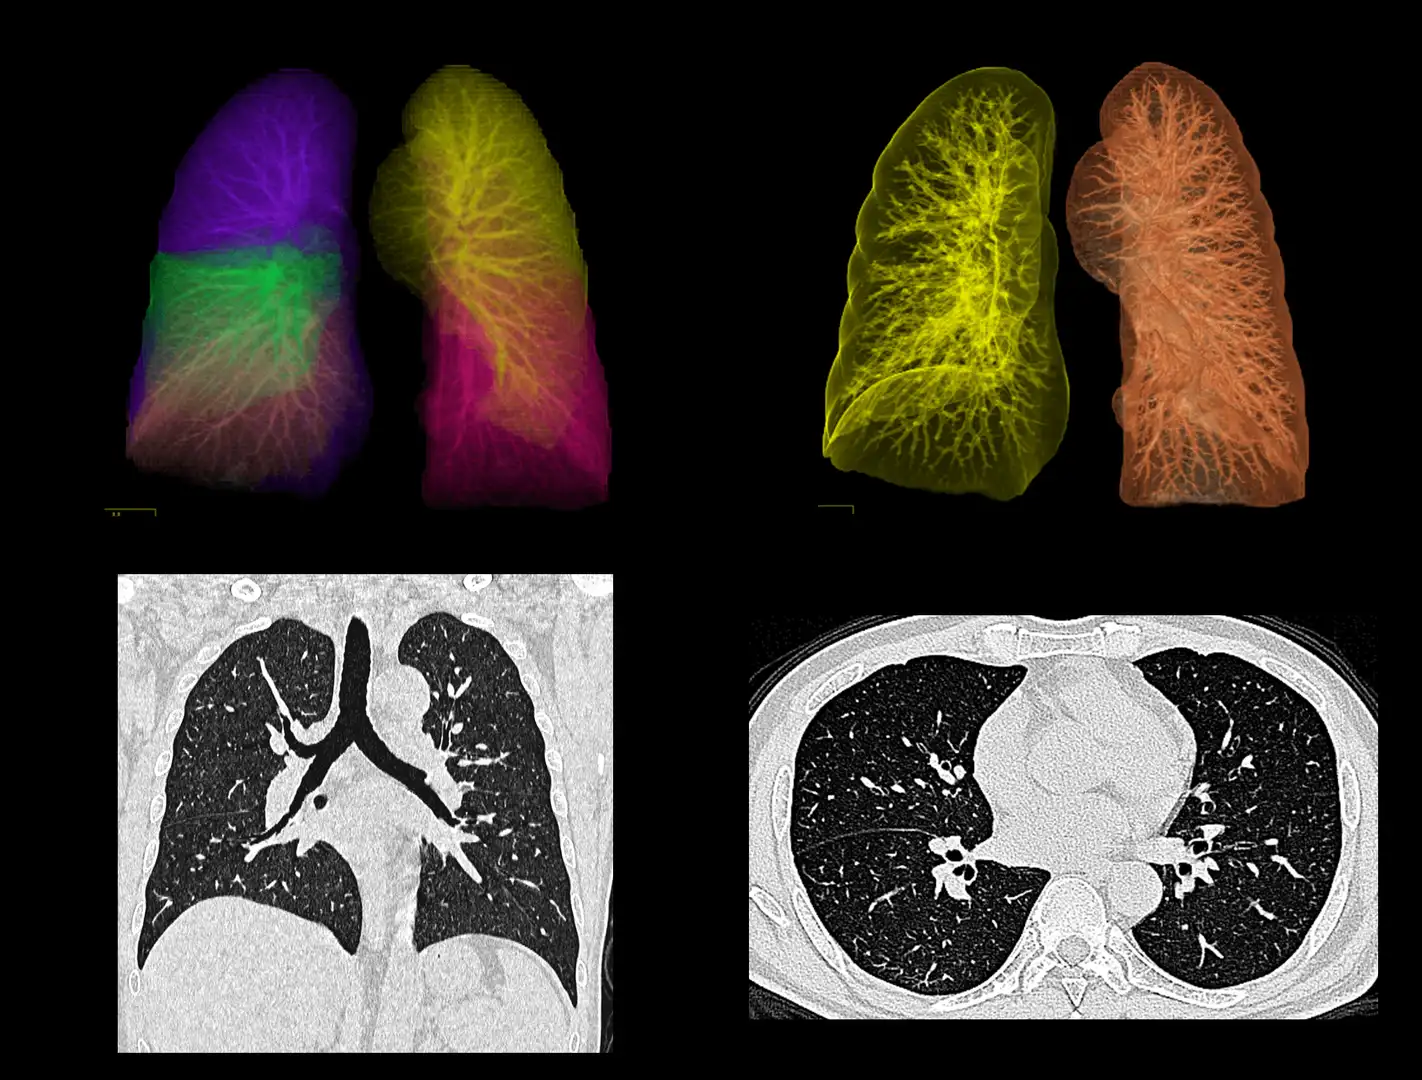

- Tórax: pulmones, corazón y grandes vasos